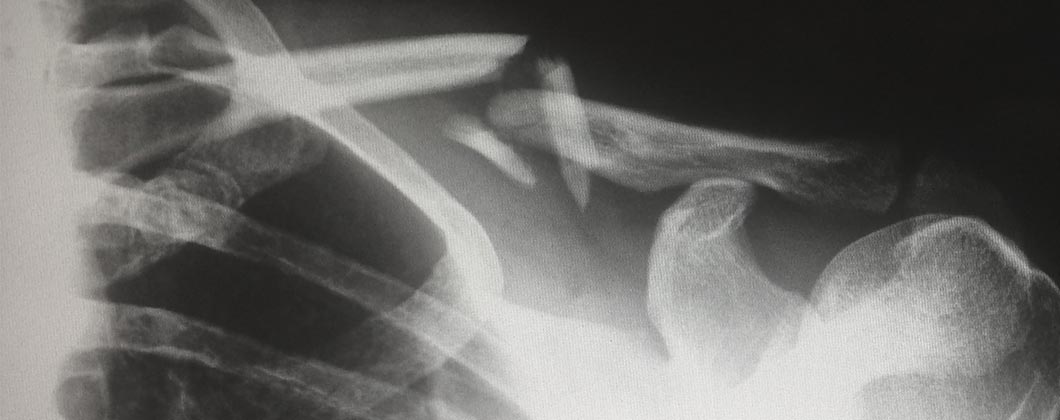

x-ray-broken-bones.jpg 2023-02-01 16:21 47K